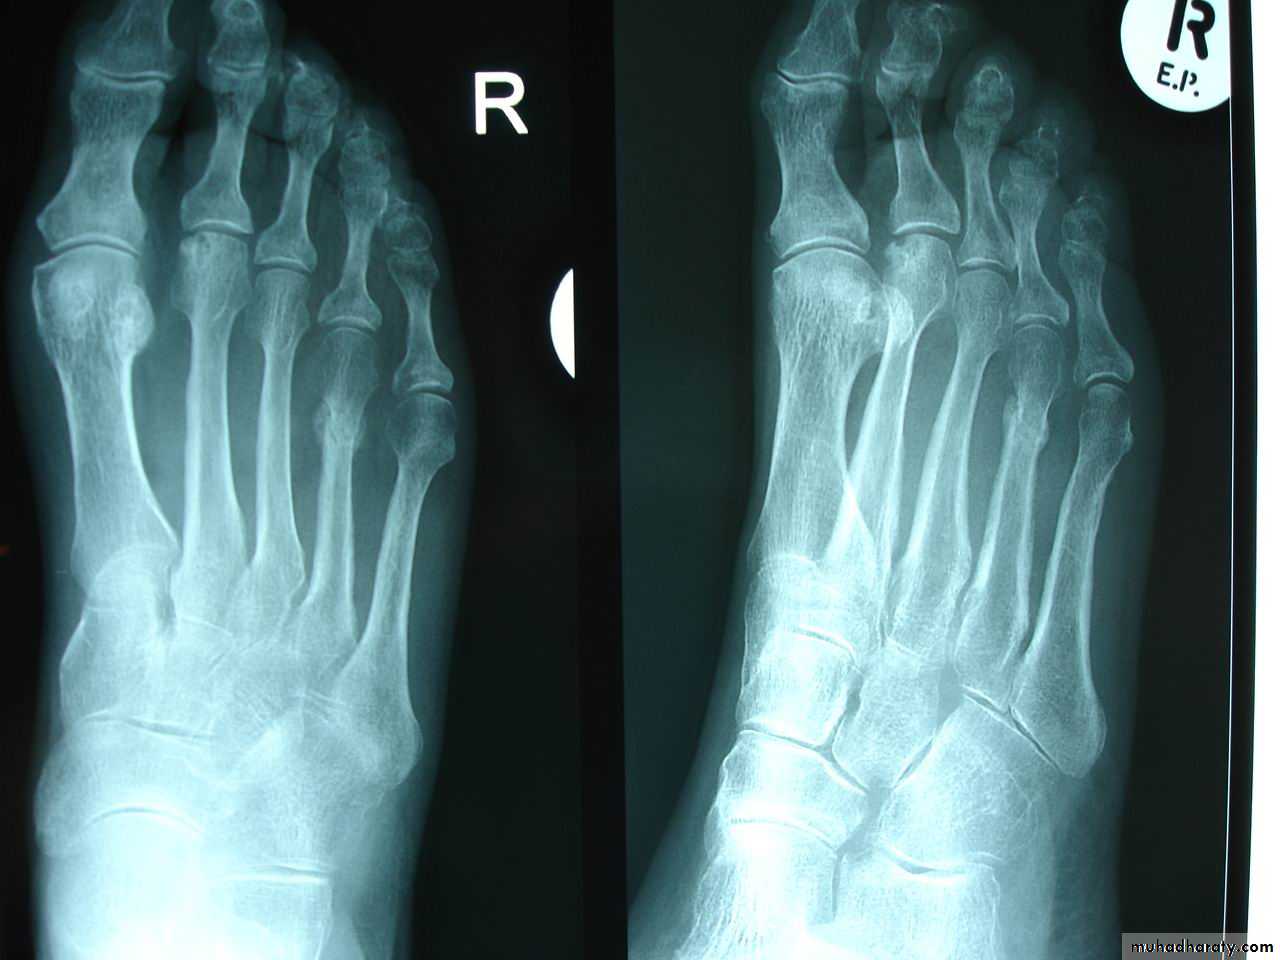

34Stress (fatigue) #

# that occurs in normal bone by repetitive stresses

> in athletes, ballet dancers & military recruits

Common sites: pars interarticularis of L5, FN, proximal tibial shaft, distal fibular shaft,calcaneum, MTBs

XR: early : -ve… few weeks : transverse defect ± periosteal new bone

Bone scanDDx: OM, OSa

Tx :immobilize & avoid painful activity